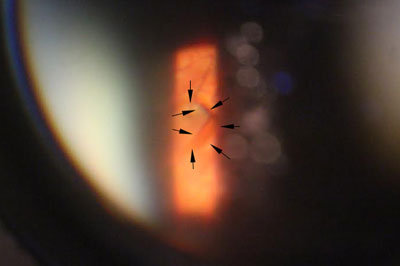

隨著激光技術的發展,近年已發展出激光治療飛蚊症,用於把較大和集中的玻璃體浮游物打散,以達到改善和消除飛蚊症狀,過程約十五至二十分鐘,沒有痛楚,並可於局部麻醉下進行。但並不是所有患有飛蚊症的人均適合做激光治療,如「飛蚊」物質較鬆散或位置太接近黃斑或晶體,便不適合進行此類激光治療,以免導致白內障或黃斑受損等併發症。